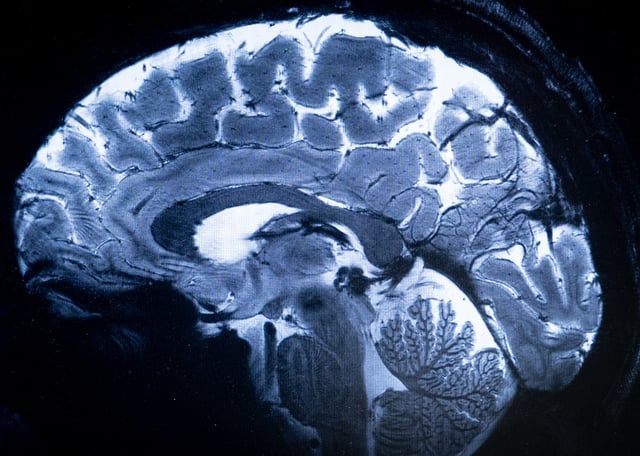

محمد الرخا - دبي - الأربعاء 3 أبريل 2024 02:22 صباحاً - التقط أقوى جهاز تصوير بالرنين المغناطيسي في العالم، بالقرب من باريس، صوره الأولى للدماغ البشري، ويُتوقَع أن يتيح فهماً أكبر لوظائفه وبعض الأمراض التنكسية العصبية أو النفسية.

صور طبية بوساطة جهاز الرنين المغناطيسي الحديثأ ف ب

ويصل المجال المغناطيسي لهذا المغناطيس الاستثنائي إلى 11,7 تيسلا، مما يتيح الحصول على صور أكثر دقة بعشر مرات من تلك المنتجة حاليا في المستشفيات، حيث لا تتجاوز قوة التصوير بالرنين المغناطيسي 3 تيسلا.

وعلى شاشة ألكسندر فينيو تتم مقارنة الصور المقطعية للدماغ بما كان ليوفره تصوير بالرنين المغناطيسي بقوة 3 أو 7 تيسلا.

وقال فينيو "باستخدام هذا الجهاز، يمكننا رؤية الأوعية الصغيرة جداً التي تغذي القشرة الدماغية، أو تفاصيل المخيخ التي كانت غير ظاهرة تقريباً حتى الآن".